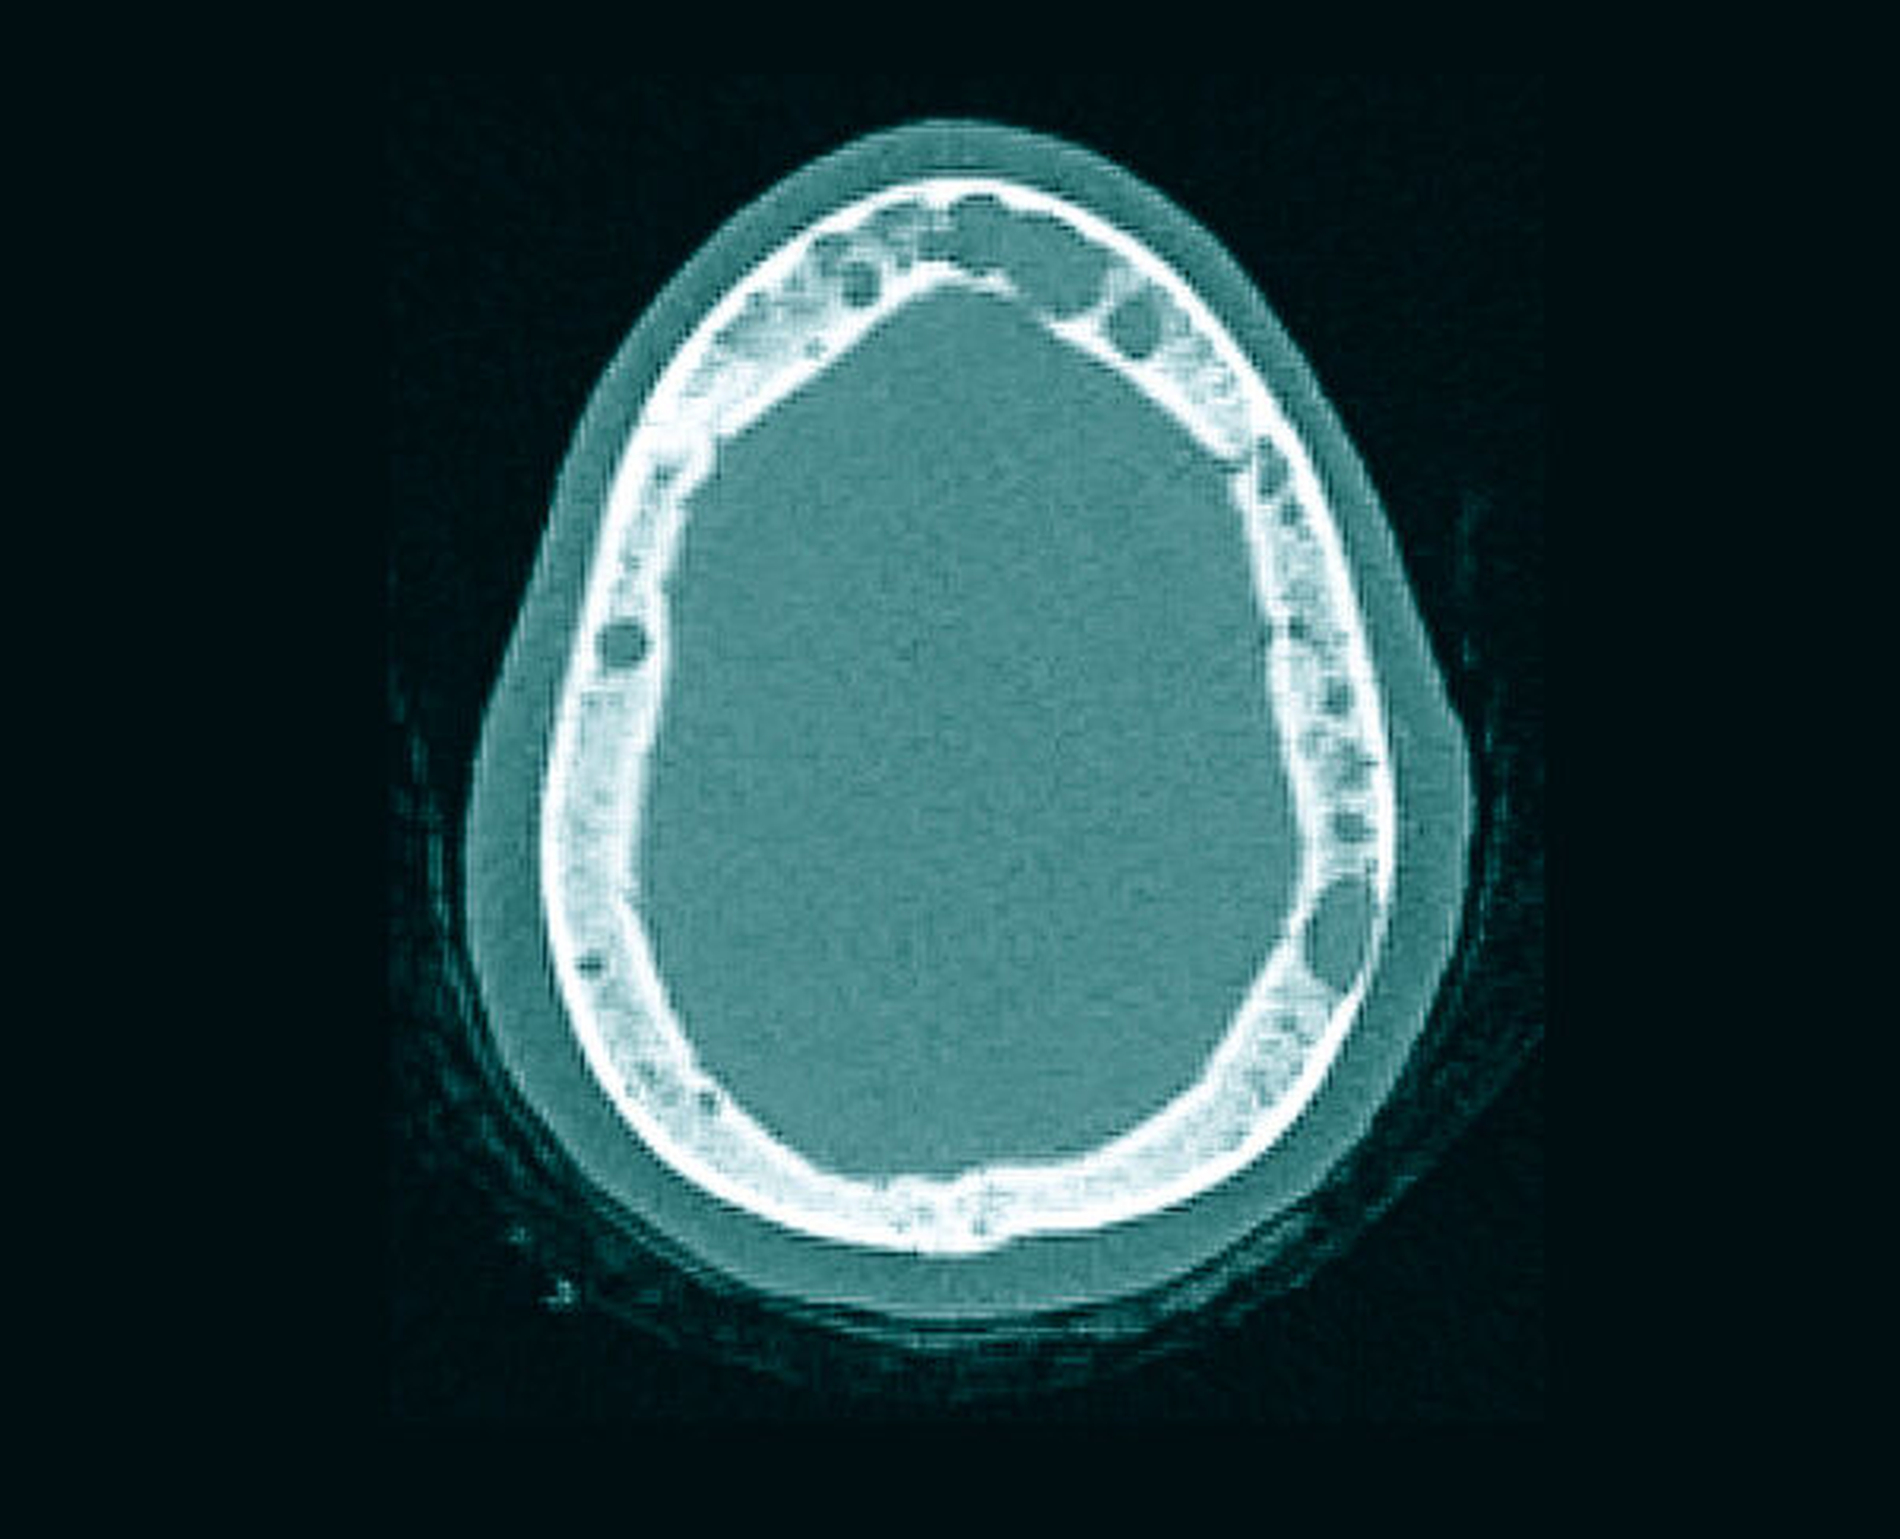

Das Orthopantomogramm zeigte eine auffällige, homogene, scharf begrenzte osteolytische Veränderung in regio 43 bis 46 ohne Resorption der angrenzenden Zahnwurzeln, allerdings mit Destruktion der Corpusunterkante korrespondierend zur klinisch evidenten Auftreibung des Unterkiefers. Daneben waren weitere osteolytische Läsionen zu verzeichnen, die sich subtotal über die gesamte Mandibula verteilten (Abbildung 1). Die Computertomografie des Unterkiefers bestätigte das Vorliegen multipler disseminierter osteolytischer Prozesse (Abbildung 4).

Anhand spezifischer Laboruntersuchungen wie Eiweißelektrophorese und Immunfixation einschließlich Knochenmarkspunktion konnte die Diagnose Multiples Myelom gesichert werden. Die Ganzkörper-Low-Dose-CT ergab einen multifokalen Befall weiterer Teile des Skeletts (Abbildung 5) mit Kompressionsfraktur des dritten Halswirbelkörpers. Eine gezielte kombinierte Therapie mit Bortezomib, Lenalidomid, Dexamthason sowie Denosumab wurde in kurativer Intention binnen einer Woche eingeleitet. Zahnärztlich-chirurgischer Sanierungsbedarf ergab sich bezüglich der Einleitung der antiresorptiven Therapie nicht. Eine konservierende sowie eine Parodontaltherapie über den Hauszahnarzt wurden empfohlen.

Bei Erkrankungen des hämatopoetischen und des lymphatischen Systems ist zum einen die Histiozytose X (Langerhans-Zell-Granulomatose) zu nennen, die meist im Kindes- oder im Jugendalter auftritt und multifokale Osteolysen hervorrufen kann [Kim et al., 2019]. Zum anderen sind Lymphome, insbesondere das solitär auftretende intraossäre Lymphom und das Plasmozytom, zu erwähnen [Wen et al., 1988]. Letzteres wird bei multiplem Auftreten wie im vorliegenden Fall als Multiples Myelom bezeichnet. Zahlreiche osteolytische, scharf begrenzte Herde unterschiedlicher Größe verleihen dem Knochen im Rahmen des Multiplen Myeloms ein schrotkugelartig ausgestanztes Aussehen [Witt et al., 1997]. Die hämatopoetisch aktive Mandibula kann dabei betroffen sein. Das Auftreten von Veränderungen im Bereich des Unterkiefers als Erstmanifestation eines Multiplen Myeloms ist wiederum selten [Goetze et al., 2014].